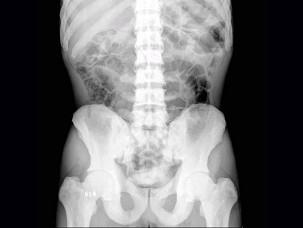

问题 男,38岁,生活在沿海一带,腰背部疼痛半年余,根据所提供的图像,最可能诊断是?(?)

选项 A.石骨症 B.肾性骨病 C.氟骨症 D.成骨性转移瘤 E.骨纤维异常增殖症

答案 C